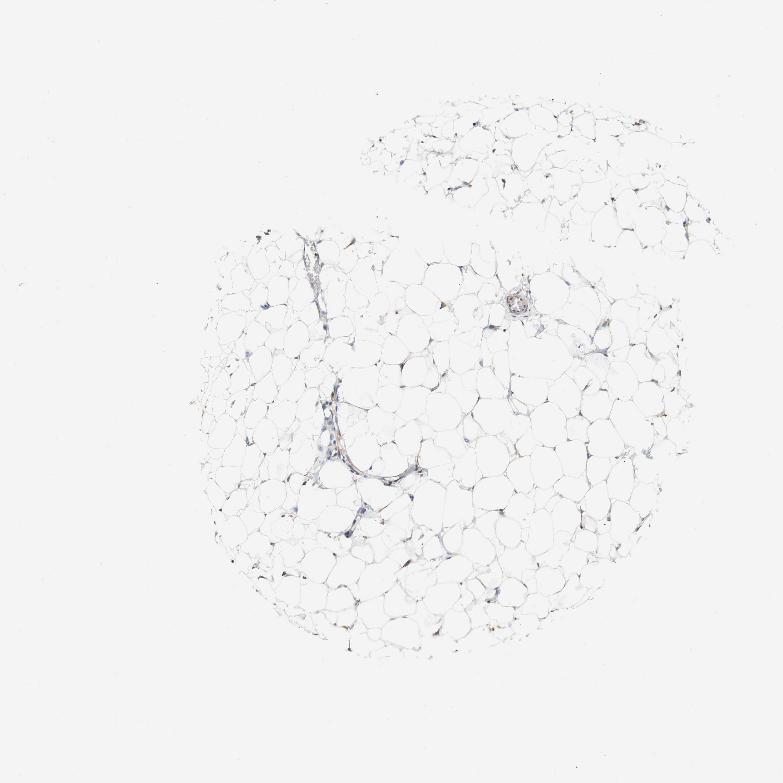

SOFT TISSUE 2 - Antibody stainingi

Antibody staining in the annotated cell types in the current human tissue is reported as not detected, low, medium, or high, based on conventional immunohistochemistry profiling in selected tissues. This score is based on the combination of the staining intensity and fraction of stained cells.

Each image is clickable and will lead to virtual microscopy that enables deeper exploration of all samples and also displays staining intensity scores, fraction scores and subcellular localization as well as patient and tissue information for each sample.

Antibody HPA011811

Fibroblasts Low

Peripheral nerve Low